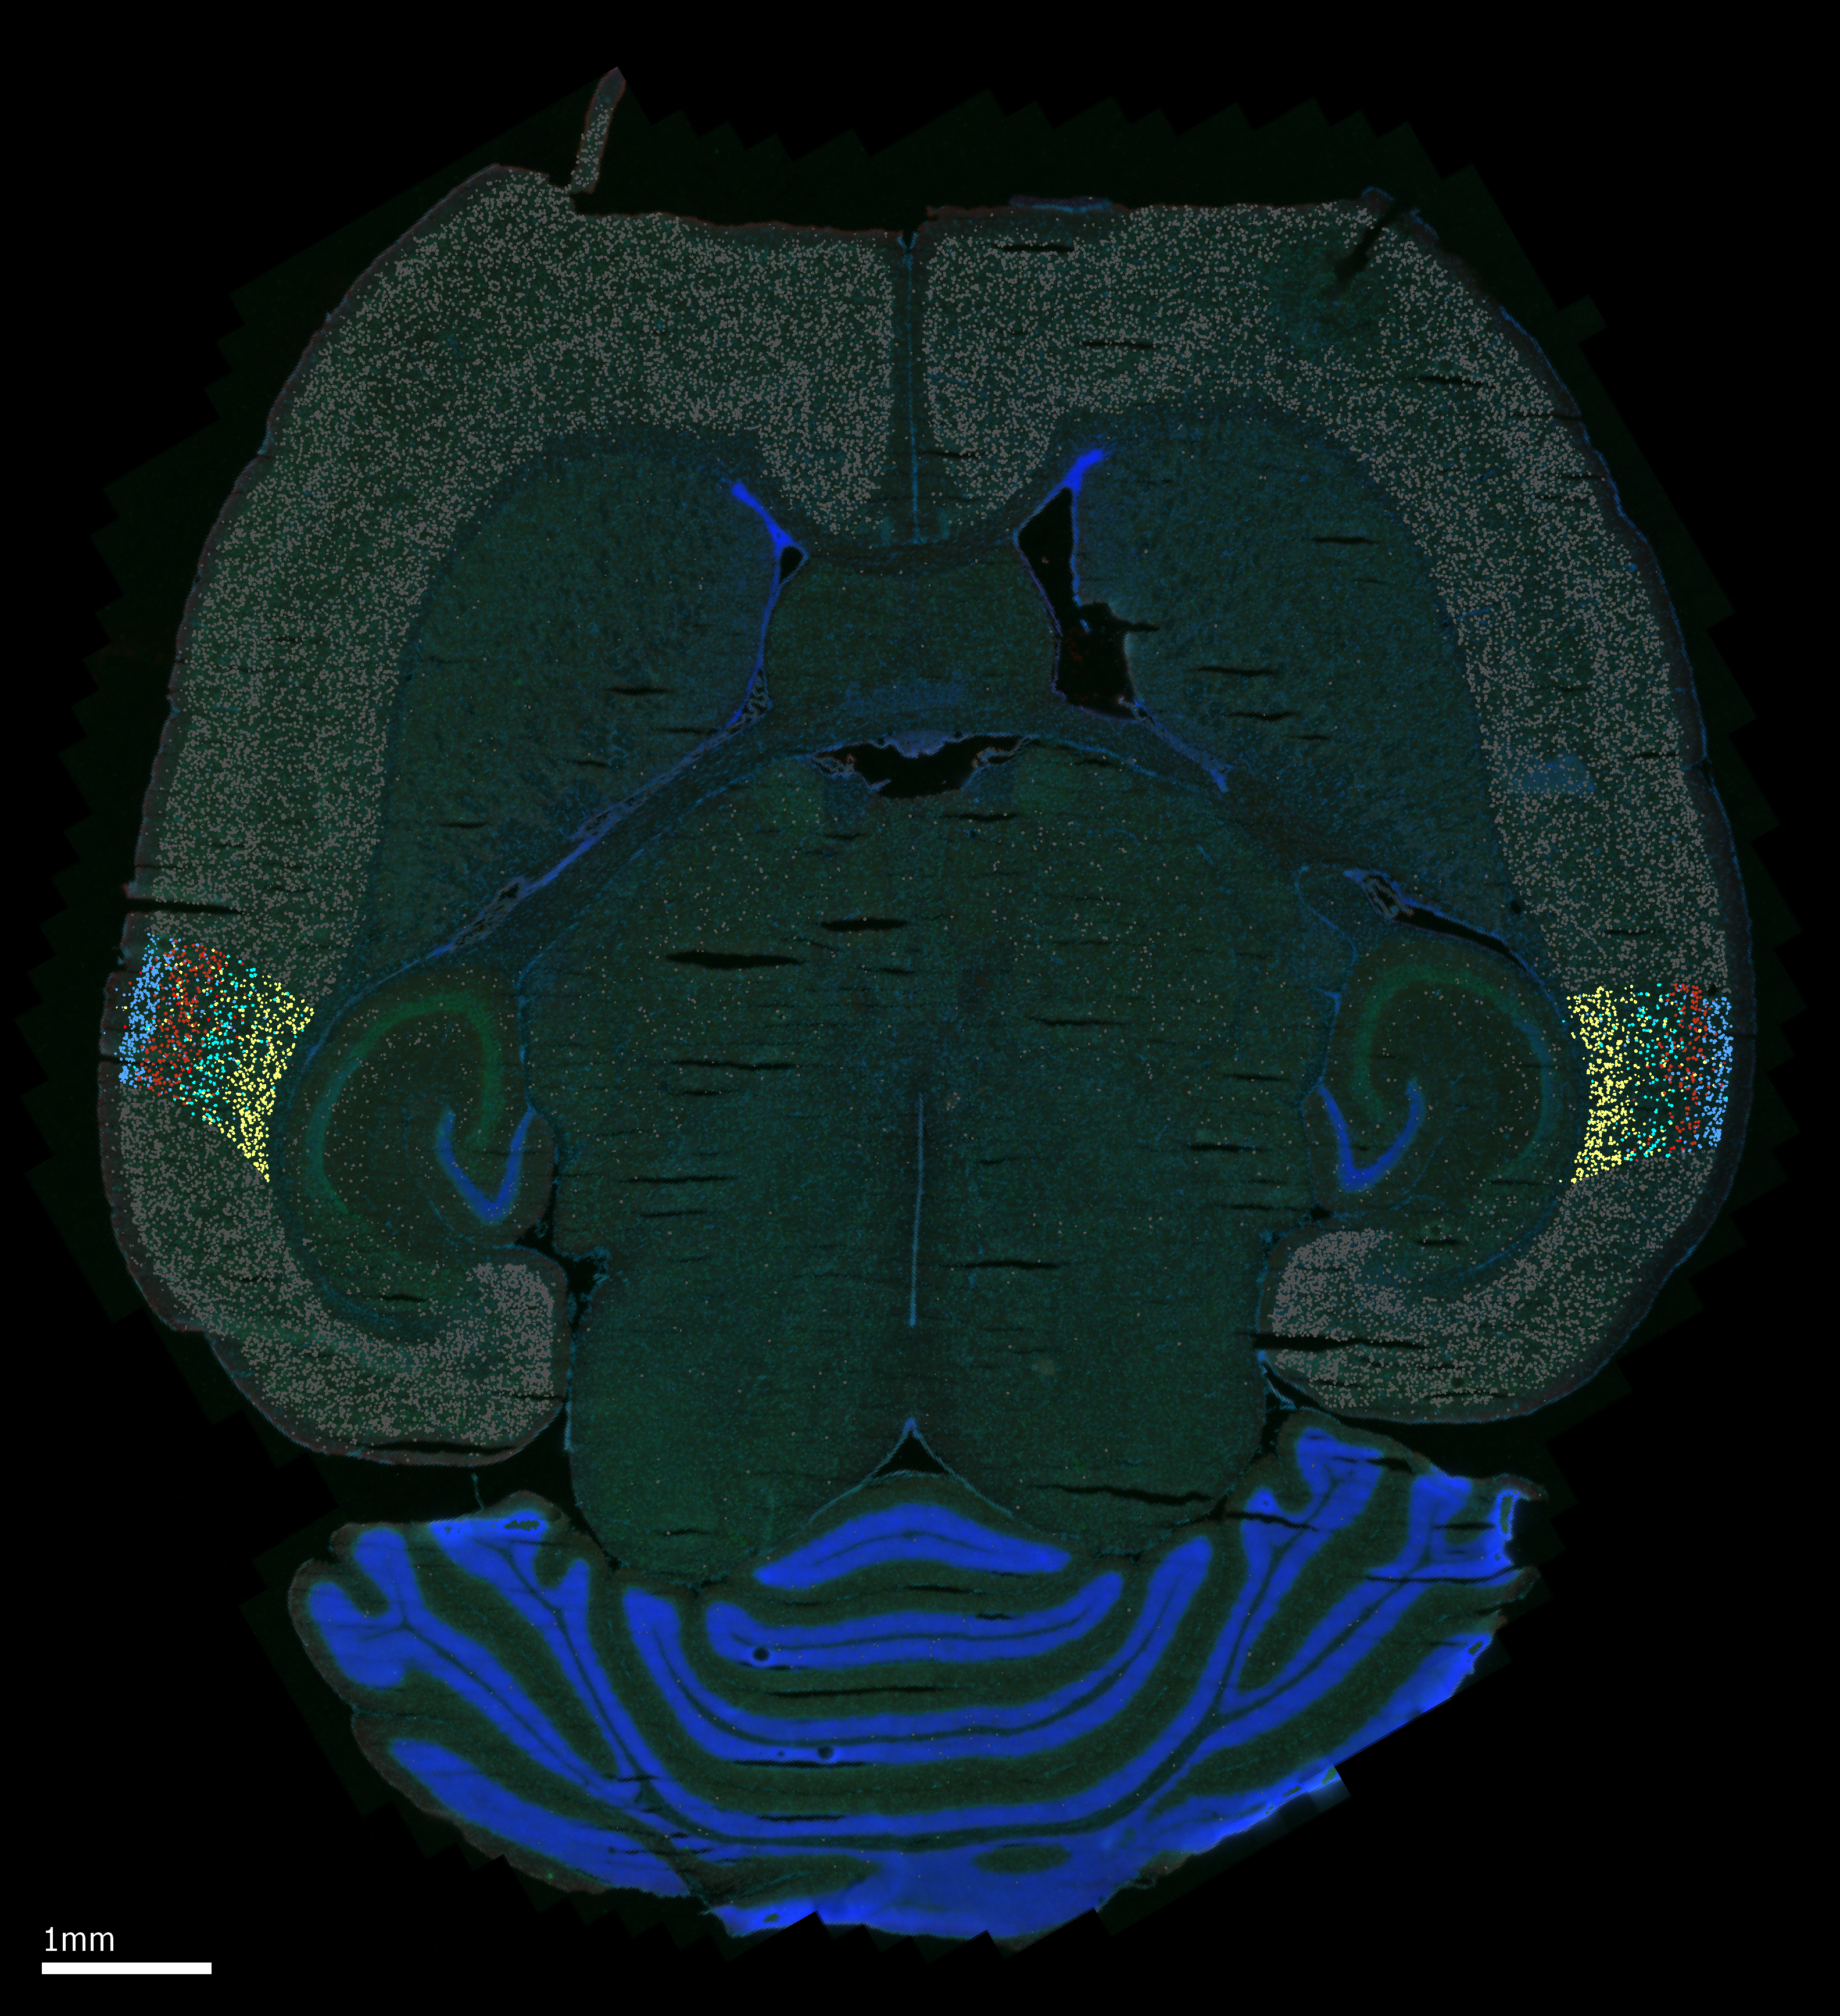

The mechanisms by which the auditory cortices develop unique sound processing capabilities remain unknown. Recent research conducted in our lab has indicated notable variations in the maturation trajectory of the auditory cortices. To gain insights into the molecular pathways responsible for these differences, we investigate changes in gene expression between the auditory cortices using spatial transcriptomics.